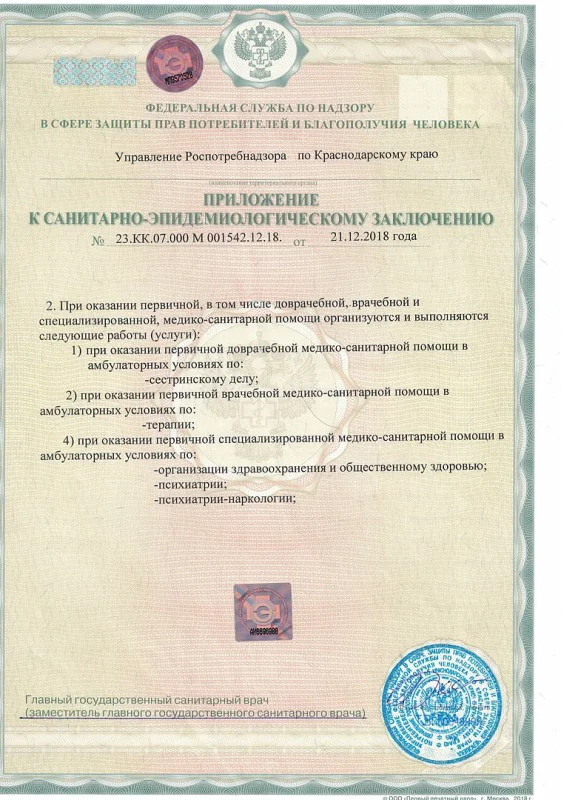

Лицензия на осуществление медицинской деятельности

Лицензия на осуществление медицинской деятельности

Лицензия на осуществление медицинской деятельности

Лицензия на осуществление медицинской деятельности

Лицензия на осуществление медицинской деятельности

Лицензия на осуществление медицинской деятельности

Лицензия на осуществление медицинской деятельности

Лицензия на осуществление медицинской деятельности